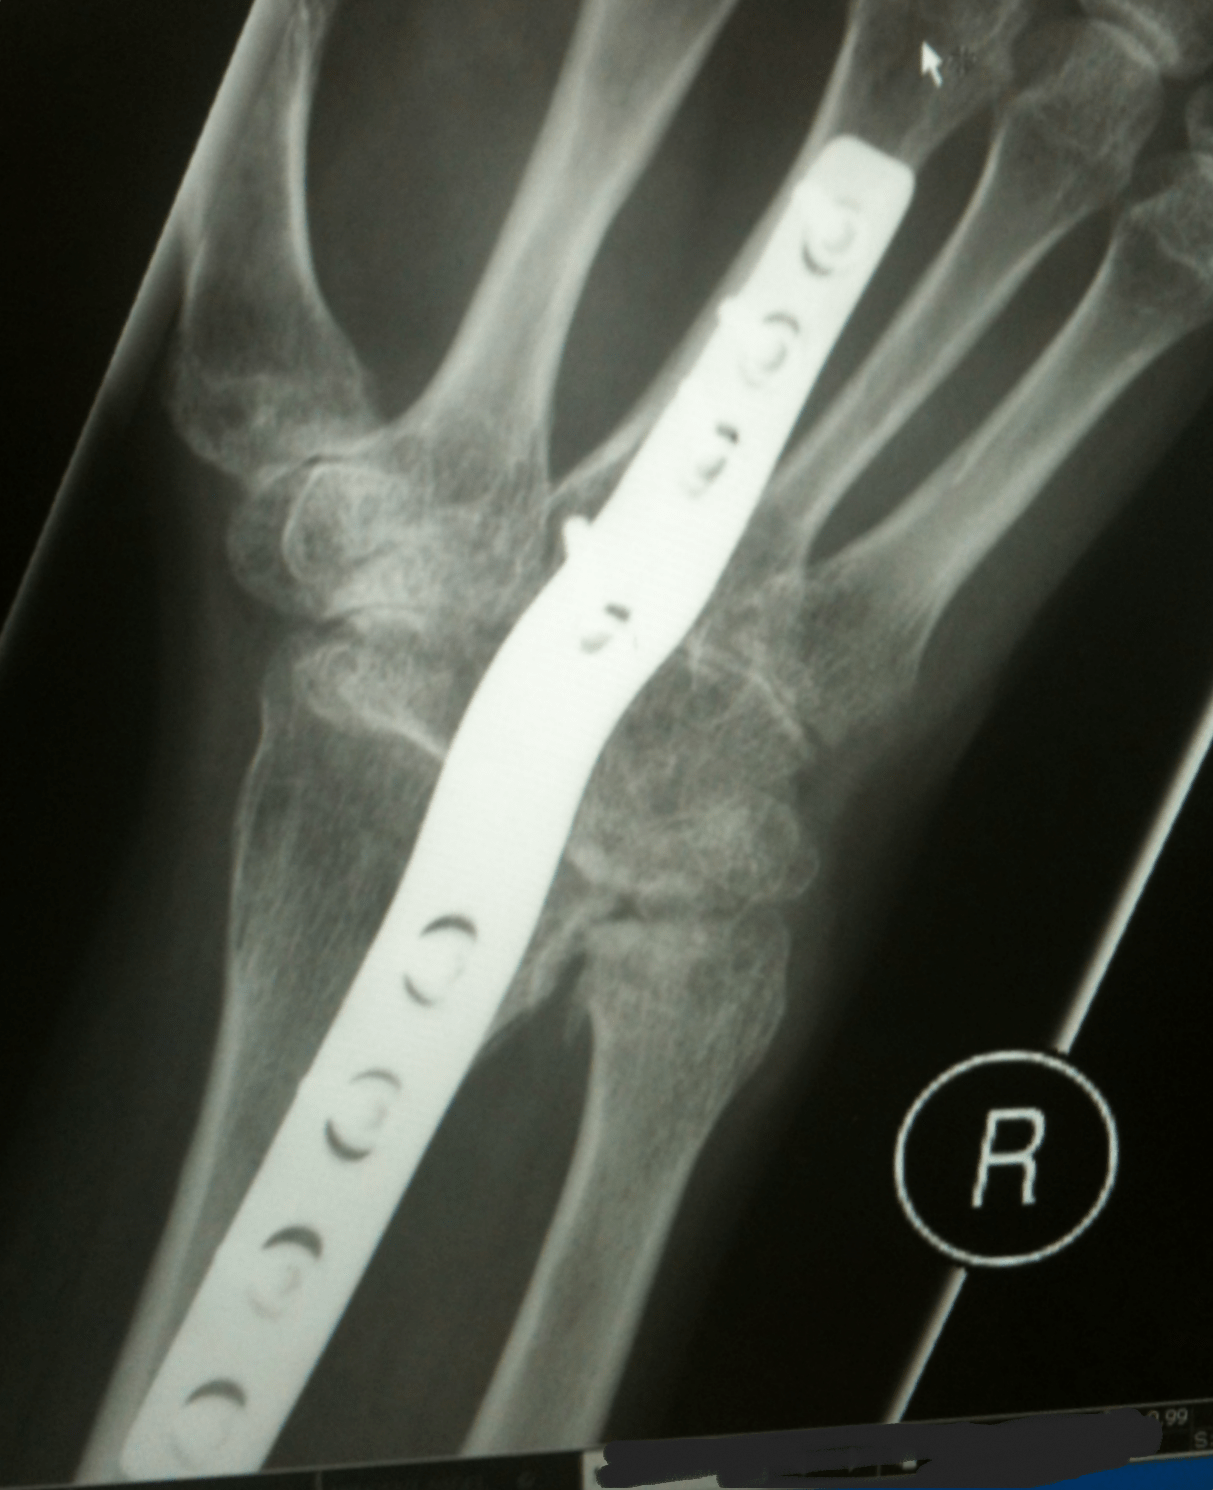

Xray image of Right wrist joint Ap and Lateral view for diagnosis Arthritis In Wrist X Ray Rheumatoid arthritis (ra) is a chronic autoimmune multisystemic inflammatory disease that affects many organs but. The physical exam will look for areas of pain, swelling and decreased motion. In this article we provide an overview of the different imaging findings of common joint diseases as a useful tool in daily musculoskeletal radiology. An arthritic joint will demonstrate narrowing of the. Arthritis In Wrist X Ray.